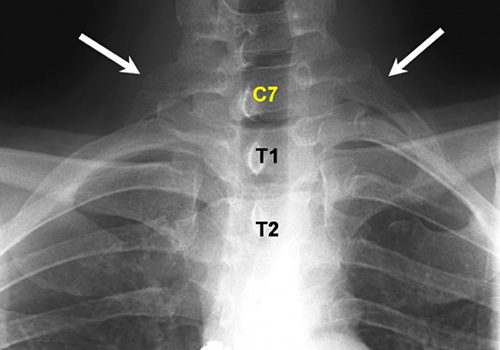

Επιπλέον πλευρά

Το χαρακτηριστικό αυτό εμφανίζονται κυρίως σε γυναίκες. Τα πλευρά αυτά εμφανίζονται συνήθως στην αυχενική περιοχή της σπονδυλικής στήλης και μερικές φορές, αν είναι αρκετά μεγάλα, μπορεί να προκαλέσουν δυσφορία.